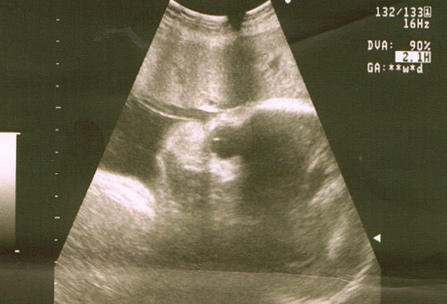

Ecografías de la semana 38 de embarazo

Ecografía semana 38: cara de perfil y placenta. Se visualiza el perfil del bebé y la placenta en cara anterior, lo que significa que está situada en la parte superior de la imagen.

Ecografía semana 38: líquido amniótico. La ecografía muestra líquido amniótico en cantidad normal, lo que es un signo de bienestar fetal.